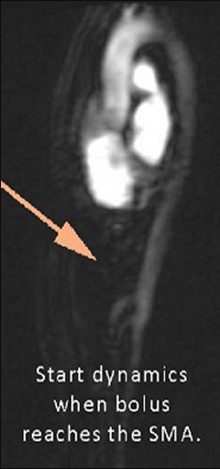

Power Inject Contrast Bolus Track Trigger when bolus reaches the SMA

Bolus track SMA